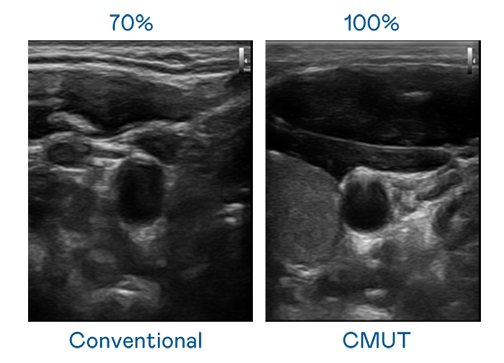

CMUT 技术是一种用电容式微机电元件来产生超音波讯号的技术。与传统 PZT 压电式技术相比,CMUT 频宽增加 30%,更宽频的超音波讯号让影像解析度大幅提升,是实现高影像品质医疗超音波扫描、促进精准医疗发展的关键技术。

大频宽带来超清晰影像

超音波影像的解析度高低,首先取决于探头能发出的讯号频宽。麻花mv星空mv梦幻mv CMUT 可提供高清晰的超音波讯号,提供高频宽、高灵敏度、影像纹理细节更高的超音波影像,协助医护人员缩短影像判读时间及利用精准的医疗影像进行诊断。